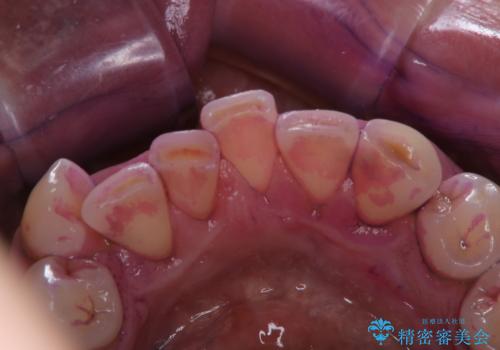

被せ物治療が終了したため全体的にクリーニングを

- 被せ物の治療が終了したためメンテナンスに入る前に全体的なチェック・クリーニングを行いました。

歯科衛生士による専門的なクリーニングPMTC(保険外治療)60分コースを行いました。

専門的な機械・材料を使用して徹底的に汚れを取り除きました。

染め出しをして、磨き残しの確認・ブラッシング指導も行いました。